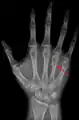

Fourth metacarpal bone

The fourth metacarpal bone (metacarpal bone of the ring finger) is shorter and smaller than the third.

A fracture of the fourth and/or fifth metacarpal bones transverse neck secondary due to axial loading is known as a boxer's fracture.[1]

A fractured right hand fourth metacarpal (boxer's fracture).